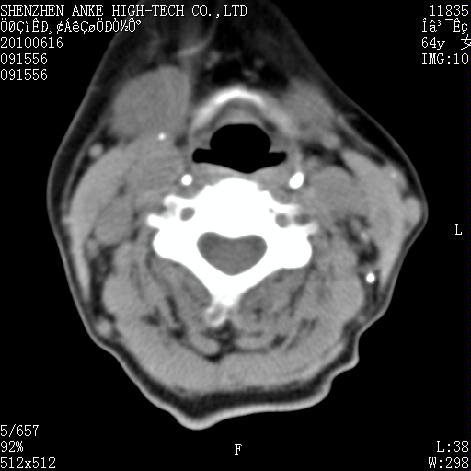

标题: CT27132:患者女,64岁,颈部及全身多处包块,现觉吞咽困难4 [打印本页]

标题: CT27132:患者女,64岁,颈部及全身多处包块,现觉吞咽困难4

右侧甲状腺占位,肿瘤可能性大,癌

右侧甲状腺癌伴右颌下腺淋巴结转移

右侧甲状腺癌伴淋巴结转移

右侧甲状腺癌伴淋巴结转移可能性大

右侧甲状腺癌伴淋巴结转移可能性大。

右侧甲状腺癌伴右颌下腺淋巴结转移!建议增强!